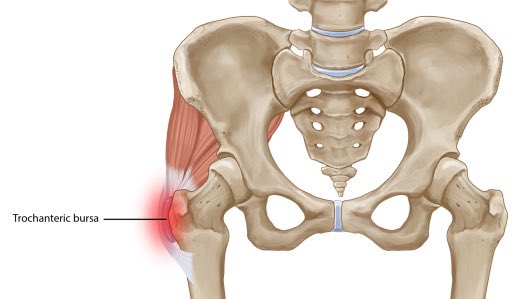

يسمى البروز العظمي في أعلى الفخذ جانبًا بالمدور الكبير، فالله خلق هناك كيس كالوسادة(جراب) يحتوي سائلًا يشبه الزيت؛ يمنع احتكاك الوتر بالعظم وأنسجة العضلة عند الحركة .

وعند حدوث حركات بأوضاع متكررة قد يلتهب هذا الكيس مسببًا ألمًا حادًا، وصعوبة عند الحركة.